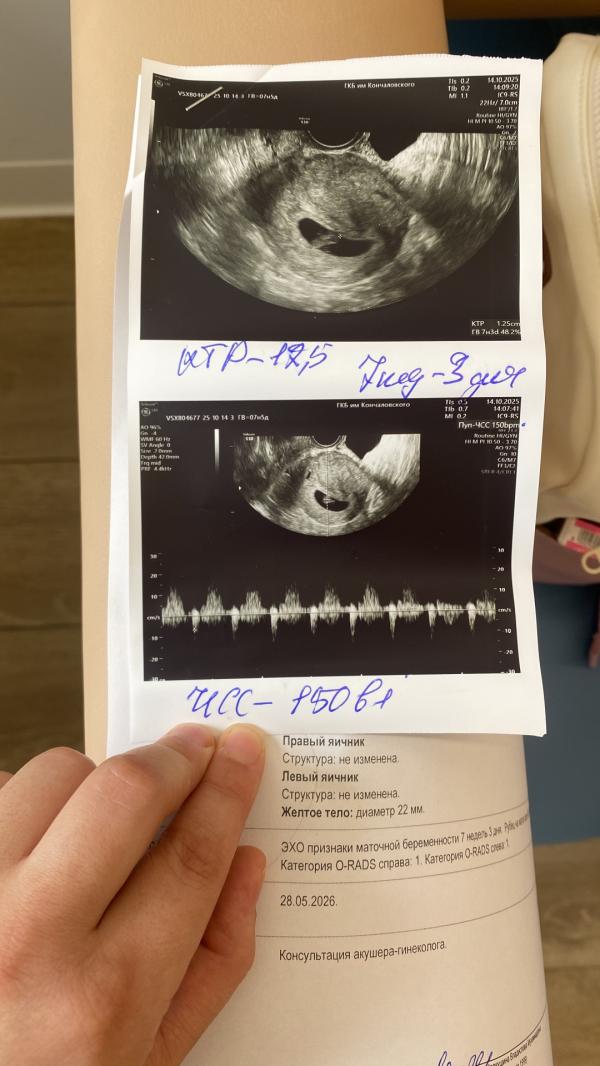

Первое узи это то которое я сделала сейчас, последние 2 фото это узи которое я делала в 7,3 недели . Эта тупорылая курица других слов у меня нет сказала что яйцо не правильной формы и поэтому это угроза прерывания беременности и размеры плода на 6-7 недель . Если что разгон у меня от меняемых до замеров по узи всего в 2 дня был . Плюс даже по ее фото что она сделала тупой поймет что плод значительно вырос от последнего узи . Горе узисты млять)) я конечно завтра схожу до жк с этим узи , но я уверена что все хорошо просто мне попалась реально курица

Я бы переделала в другом месте. Только вы знаете, на 9 неделях там уже не яйцо, а эмбрион должен быть. С большой головкой и туловищем.... Мне на 9 неделях уже КТР писали

У нее на последнем узи есть ктр просто так сфоткали, что весь документ не видно

Ну вот . Я ей говорю оно изначально у меня не круглой формы это раз , два она ставит размеры плода на 6-7 недель . Там последние 2 фото где реально размер на 7,3н было . То есть у нее еще и руки из жопы растут . На фото видно же что вырос от последнего узи